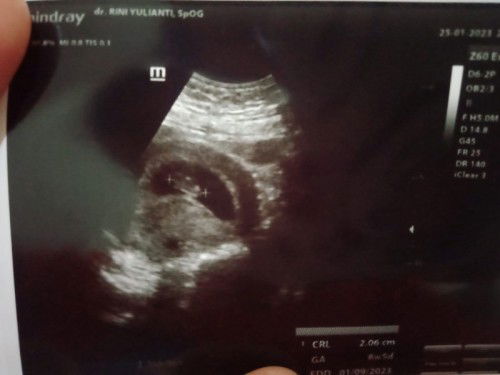

Usia kehamilan 8 minggu masih belum terlihat janin

Saya 2 Minggu yang lalu ketika usia janin 7 Minggu cek ke dokter dan USG masih terlihat kantung dan di saran kan kembali lagi besok tgl 25 Januari..apakah normal ya bund usia janin segtu belum terlihat. Dan untuk usia janin berbeda selisih antara 1 Minggu dengan hari terakhir sya mens dan alat USG dokter..menurut perkiraan saya sudah 7 Minggu tapi di hasil USG 8 minggu..Soalnya saya khawatir besok Rabu USG hasil nya kehamilan kosong 😥😥 #seriusnanya